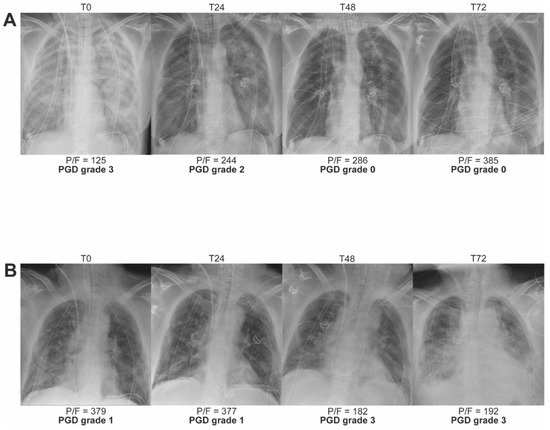

| Grade | Bilateral Alveolar Infiltrates on Chest X-ray | PaO2/FiO2 Ratio |

|---|---|---|

| PGD grade 0 | No | Any |

| PGD grade 1 | Yes | >300 |

| PGD grade 2 | Yes | 200–300 |

| PGD grade 3 | Yes | <200 |